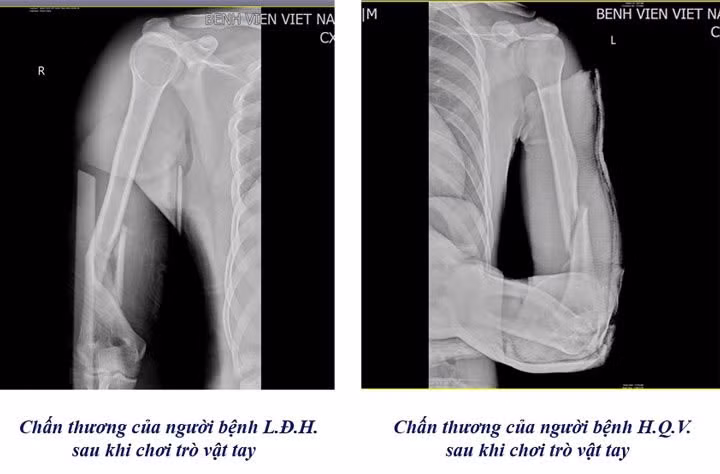

Chỉ trong vòng 1 tuần, Khoa Chấn thương Chỉnh hình & Bỏng, Bệnh viện Việt Nam – Thụy Điển Uông Bí đã tiếp nhận 3 trường hợp nhập viện do gãy xương cánh tay, nguyên nhân là từ trò chơi “vật tay”.

Theo bác sĩ Khoa Chấn thương Chỉnh hình & Bỏng cho biết, khi vật tay, lực xoay đột ngột tác động lên xương cánh tay có thể vượt ngưỡng chịu đựng, gây gãy xoắn xương cánh tay, thậm chí di lệch.

Gãy xương trên phim chụp của các bệnh nhân chơi trò vật tay - Ảnh BVCC

Có những trường hợp nhập viện trong tình trạng gãy nham nhở, gây khó khăn cho các bác sĩ trong việc đưa các mảnh xương về vị trí ban đầu, gia tăng nguy cơ tổn thương dây thần kinh quay, dây thần kinh trụ và mạch máu lân cận. Đa phần các trường hợp nhập viện đều ở độ tuổi học sinh, sinh viên.

Các trường hợp này thường phải tiến hành phẫu thuật kết hợp xương bằng nẹp vít. Đây là kỹ thuật hiện đại và phổ biến trong điều trị gãy xương cánh tay, mang lại hiệu quả cao giúp người bệnh gãy xương mau lành, cố định vững chắc vị trí gãy và tạo điều kiện thuận lợi cho quá trình liền xương.